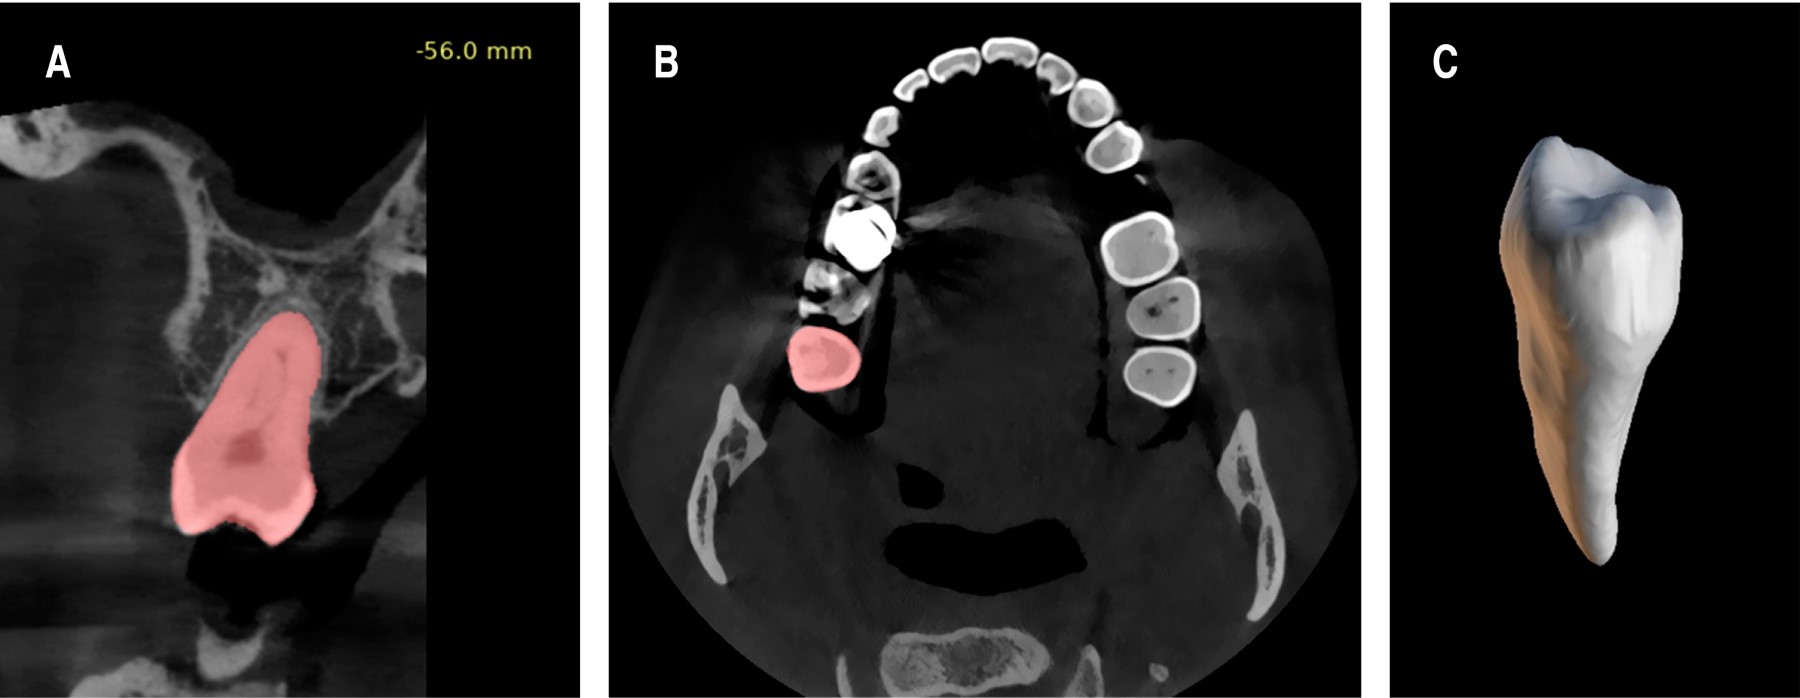

Se utilizó el visor de tomografía del programa "Blue Sky plan" desarrollado por Blue Sky Bio mediante los archivos "Digital Imaging and Communications in Medicine (DICOM)" de la tomografía computarizada de haz cónico se realizaron mediciones de las dimensiones del diente donador, en conjunto con las mediciones óseas del lecho receptor (distancia entre diente y diente) y la distancia mesio-distal entre los dientes adyacentes al mismo. Evaluando cuidadosamente las dimensiones del diente donador y del lecho receptor.

En el software de planificación digital se realizó mediante el panel de segmentación, la segmentación axial, coronal y sagital del diente donador para la creación de la reconstrucción volumétrica del diente (Figura 3A-C).

La reconstrucción volumétrica del diente donador se superpuso en el lecho receptor del modelo STL mandibular y se ubicó en la posición deseada, en infraoclusión con respecto al plano oclusal mandibular (Figura 4A). Posterior a esto, en el panel de la creación de la guía quirúrgica, se realizó la colocación de implantes digitales personalizados con una medida de oclusal de 4.5 mm y una medida apical de 4 mm con una longitud de 13 mm, para la creación de la guía de fresado del lecho receptor (Figura 4B).